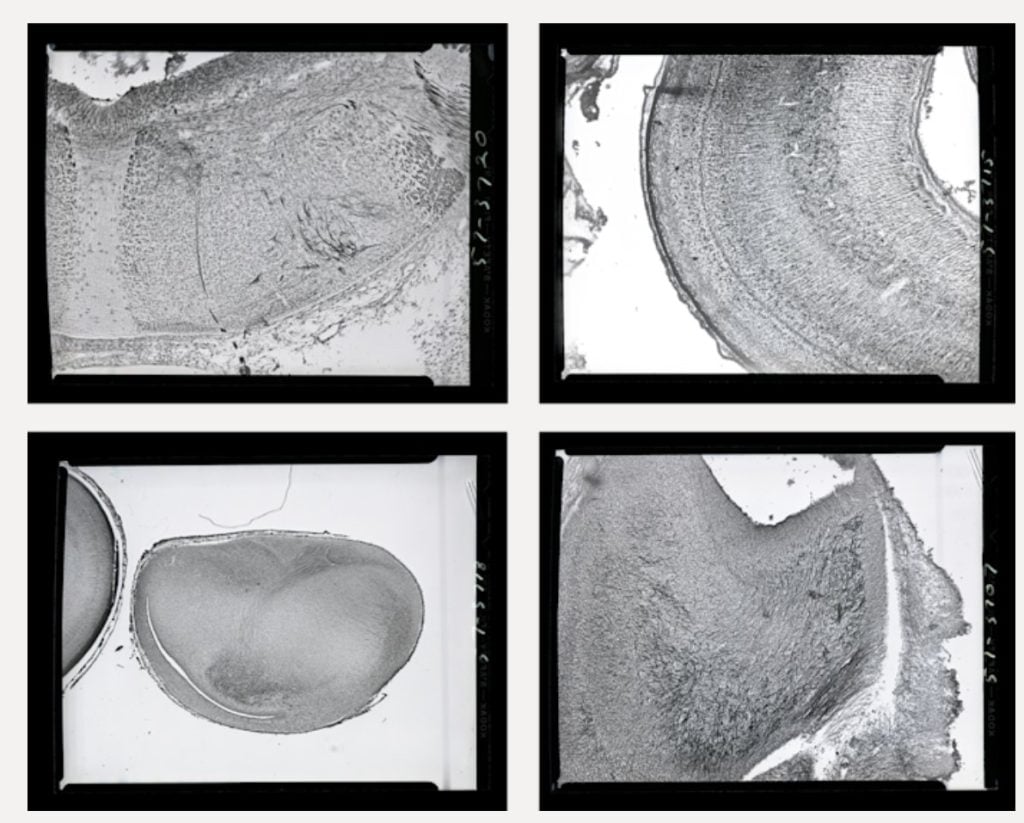

2 (of 2) Image four in a photomicroscopy series of chick embryo cerebellum and optical cortex development, dating from May 1957. These images document some of Levi-Montalcini's work studying the generation of chick optic nerves.

Photo: © Becker Medical Library, Washington University School of Medicine

1 (of 2) Image 15 in a photomicroscopy series of chick embryo cerebellum and optical cortex development, dating from May 1957. These images document some of Levi-Montalcini's work studying the generation of chick optic nerves.

© Becker Medical Library, Washington University School of Medicine

2 (of 2) Image three in a photomicroscopy series of chick embryo cerebellum and optical cortex development, dating from May 1957. These images document some of Levi-Montalcini's work studying the generation of chick optic nerves.